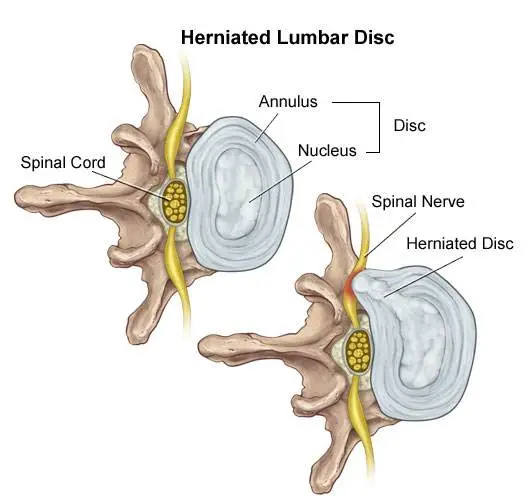

Think of the disc as a flat hard onion with strawberry jelly inside. The jelly is the nucleus while the onion layers form circular layers of hard cartilage called the annulus.

If you were to damage the annulus (onion) enough the disc gets to a point that when you bend forward, you pinch the front of the onion so it starts to bulge the onion at the back by pushing the nucleus (jelly) backwards.

Most of the layers of the onion (annulus) have been damaged but the jelly (nucleus) is under considerable pressure. The jelly (nucleus) squeezes through the layers of the annulus (onion) with the few intact layers of the onion (annulus) and the PLL (posterior longitudinal ligament) holding the jelly from spilling out. The disc is still contained by the annulus and PLL ligament. ie the balloon hasn’t popped.

Disc Extrusion is a disc bulge so large that it breaks through the last layers of the onion (annulus) and the PLL ligament pushing into the area of the spinal cord. ie. The balloon has popped. If you have an extrusion you likely have a tremendous amount of pain leg pain and usually some lower back pain.

Disc sequestration occurs when a piece of your jelly (nucleus) that breaks through the onion (annulus) and the PLL ligament has now broken off and moved away further into the spinal cord area. When you have a disc sequestration you have a tremendous amount of leg pain and some lower back pain.

There are two types of surgery available for slipped discs. Discectomy and spinal fusion. This surgery involves cutting out the piece of the disc that is protruding out and pushing on the spinal cord or nerve.

Spinal Fusion removes the disc herniation, jelly (nucleus), and most of the annulus (onion). Bone from the pelvis is then transplanted where your disc was so that the two vertebrae become one.